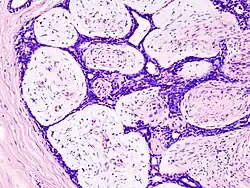

Histologisch zeigt sich ein Proliferat aus lockerem zellulärem Bindegewebe, in das in variablem Umfang gangartige epitheliale Strukturen eingelagert sind (biphasischer Aufbau). Das Stroma besteht dabei aus Zellen mit spindeligen Kernen, die keine wesentliche Pleomorphie und kaum Mitosefiguren zeigen. Die Gangstrukturen erscheinen entweder als schlitzförmige, komprimierte, elongierte Epithelformationen (intrakanalikuläres Muster) oder kleinere drüsenartige Gebilde, die konzentrisch von Stroma umgeben werden (perikanalikuläres Muster). Beide Muster kommen auch in Kombination vor und repräsentieren möglicherweise nur unterschiedliche Schnittebenen ein und derselben Läsion im histologischen Bild. Dem Wachstumsmuster kommt dabei keinerlei prognostische Bedeutung zu. In wechselndem Umfang können eine myxoide Umwandlung des Stromas oder Kalzifikationen vorhanden sein (regressive Veränderungen).